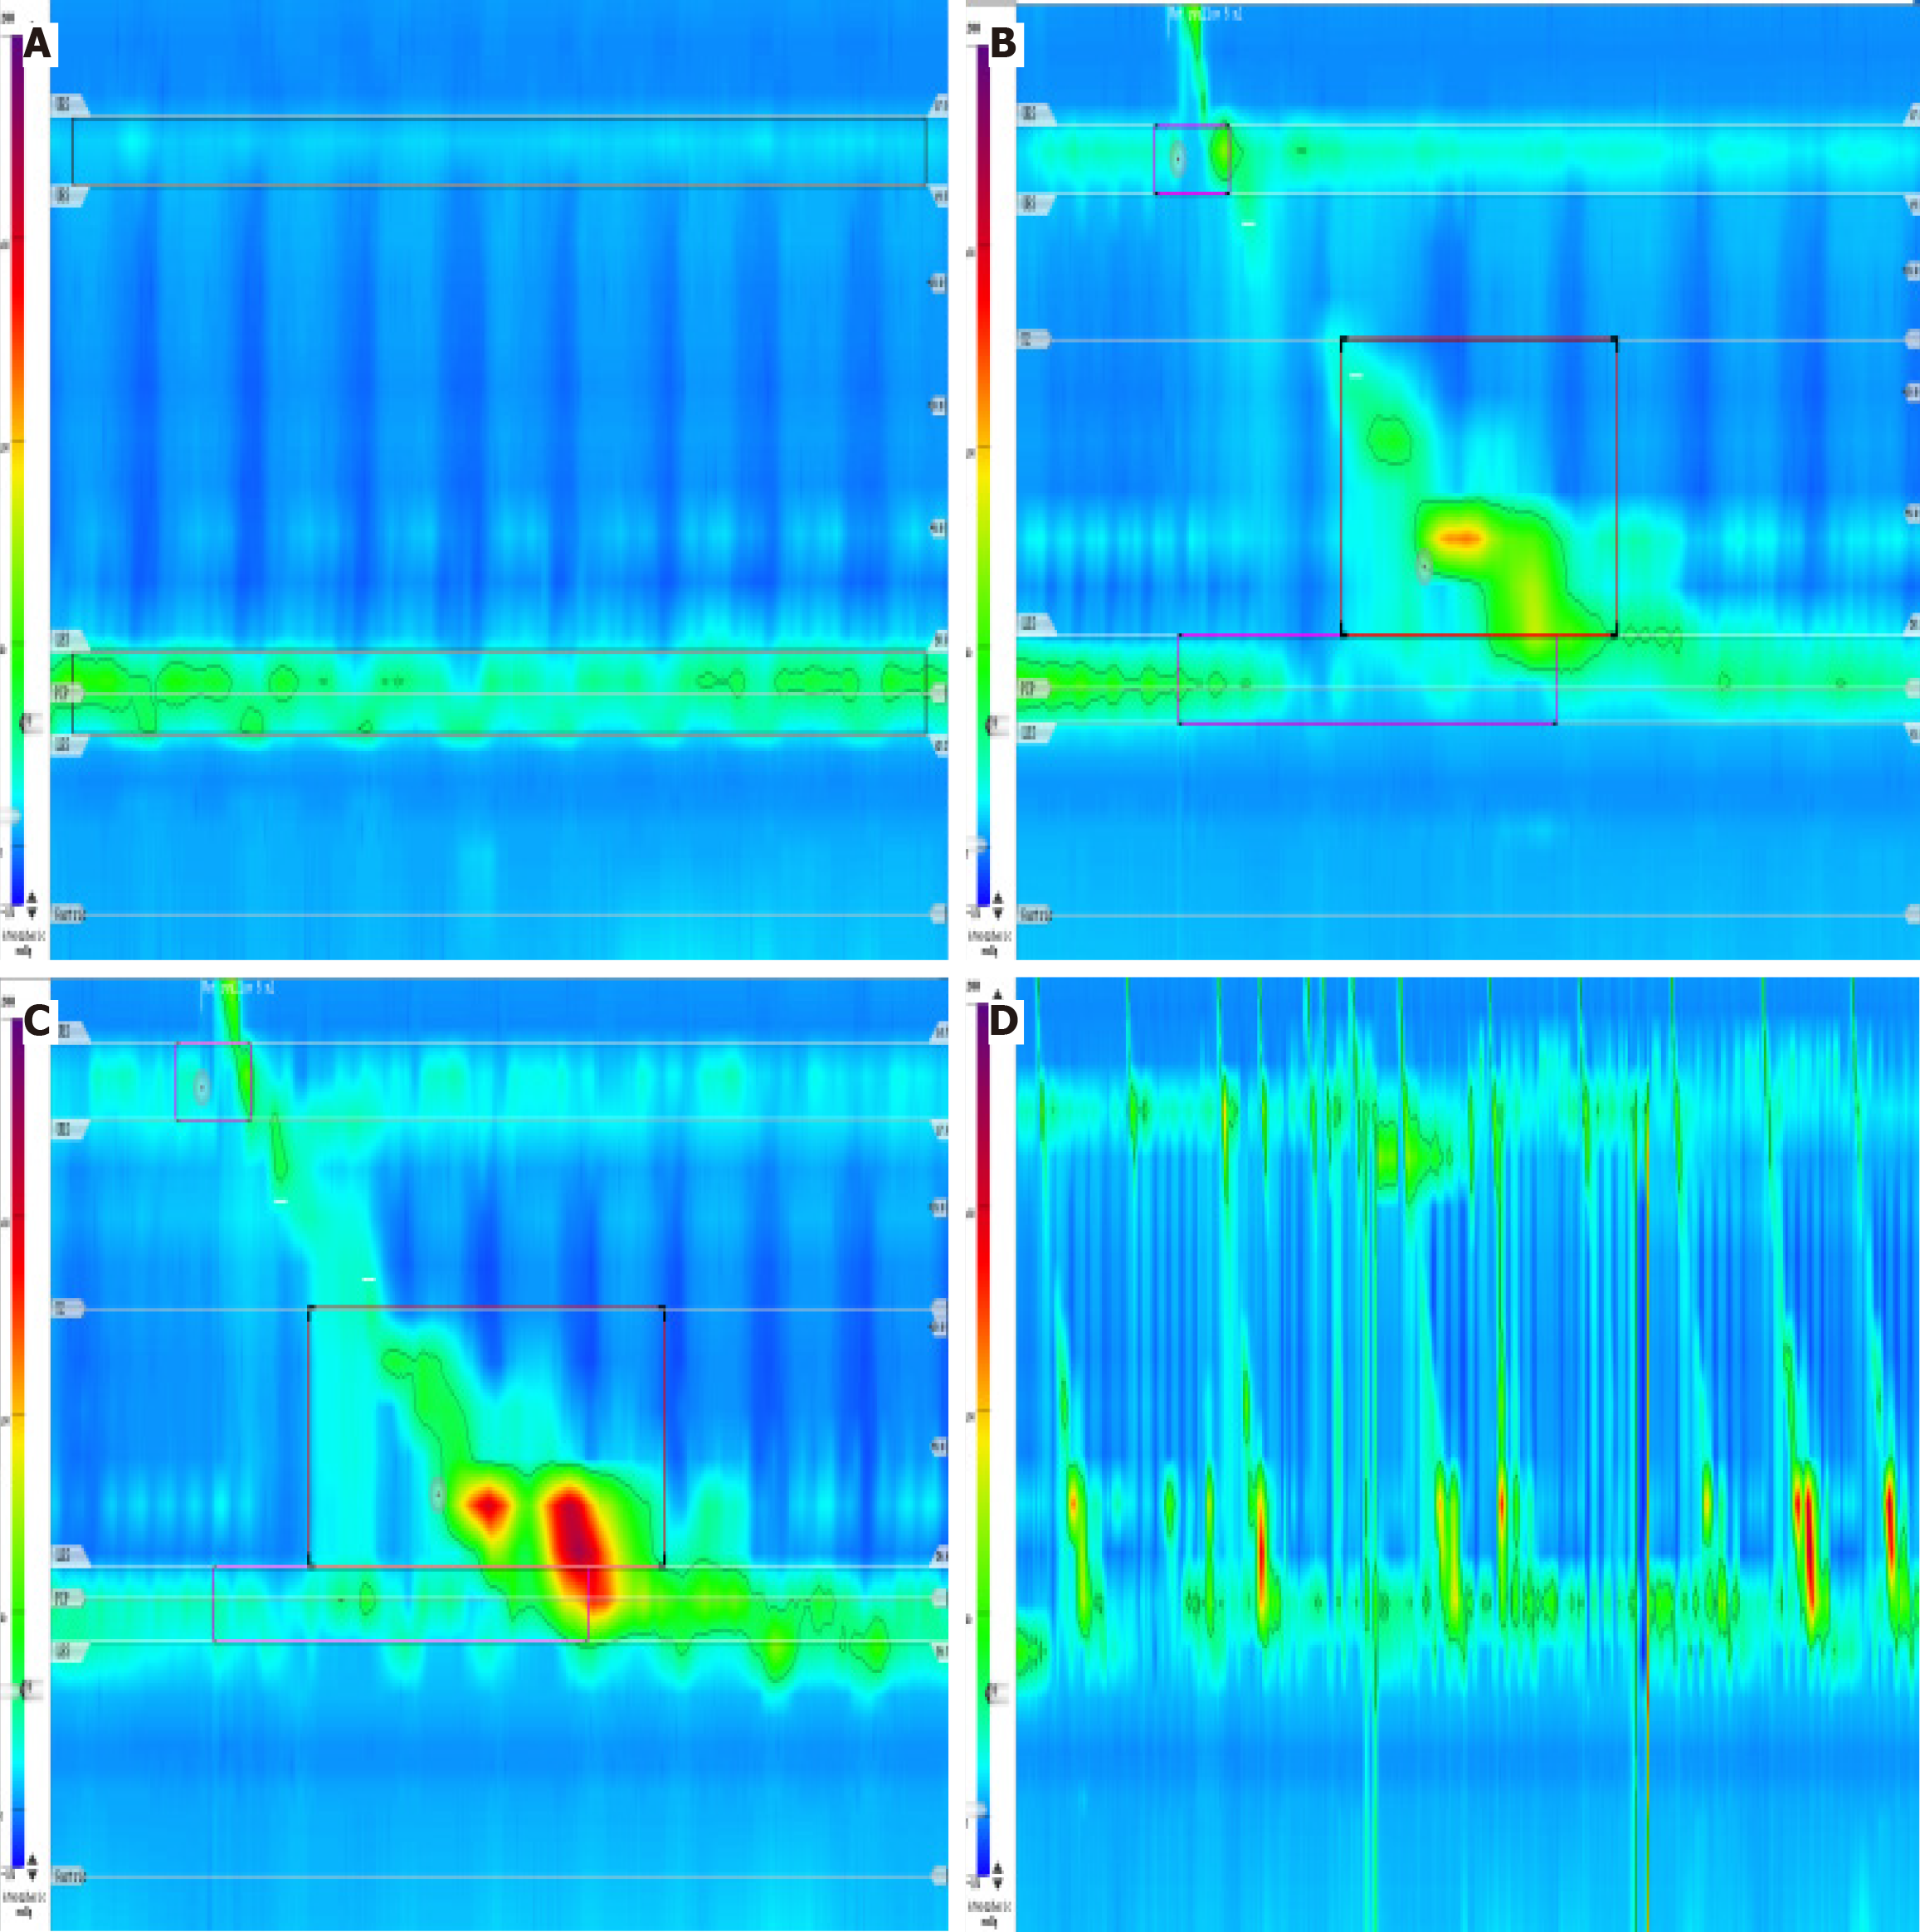

Figure 4 Esophageal manometry.

A: Static pressure: At rest, the upper esophageal sphincter pressure was low (8 mmHg in this patient, normal value 33-180 mmHg) and the low esophageal sphincter pressure was normal (27 mmHg in this patient, normal value 10-45 mmHg); B: 5 mL wet swallow: While normal 4s integrated relaxation pressure and normal distal contractile integral suggest normal peristalsis in the body of the esophagus, an interruption of the contraction wave on the 20 mmHg isobaric line with a defect length greater than 5 cm (6.5 cm) suggests segmental contraction; this swallow was ineffective; C: 5 mL wet pharynx: Normal 4s integrated relaxation pressure, normal distal contractile integral, distal latency, and maximal interruptions are in the normal range, suggesting normal esophageal motility; D: Comprehensive analysis: The patient performed 10 5-mL wet swallows, with 6 (60%) normal contractions (450 mmHg.s.cm < distal contractile integral < 8000 mmHg.s.cm) and 6 (60%) ineffective swallows (including 2 peristaltic failures, 2 weak contractions, and 2 fragmentary contractions). This suggests an indeterminate ineffective esophageal motility. Performed 3 multiple rapid swallows, with the distal contractile integral after performing multiple rapid swallows being less than the mean distal contractile integral of a single swallow, suggesting poor esophageal contractile reserve function.